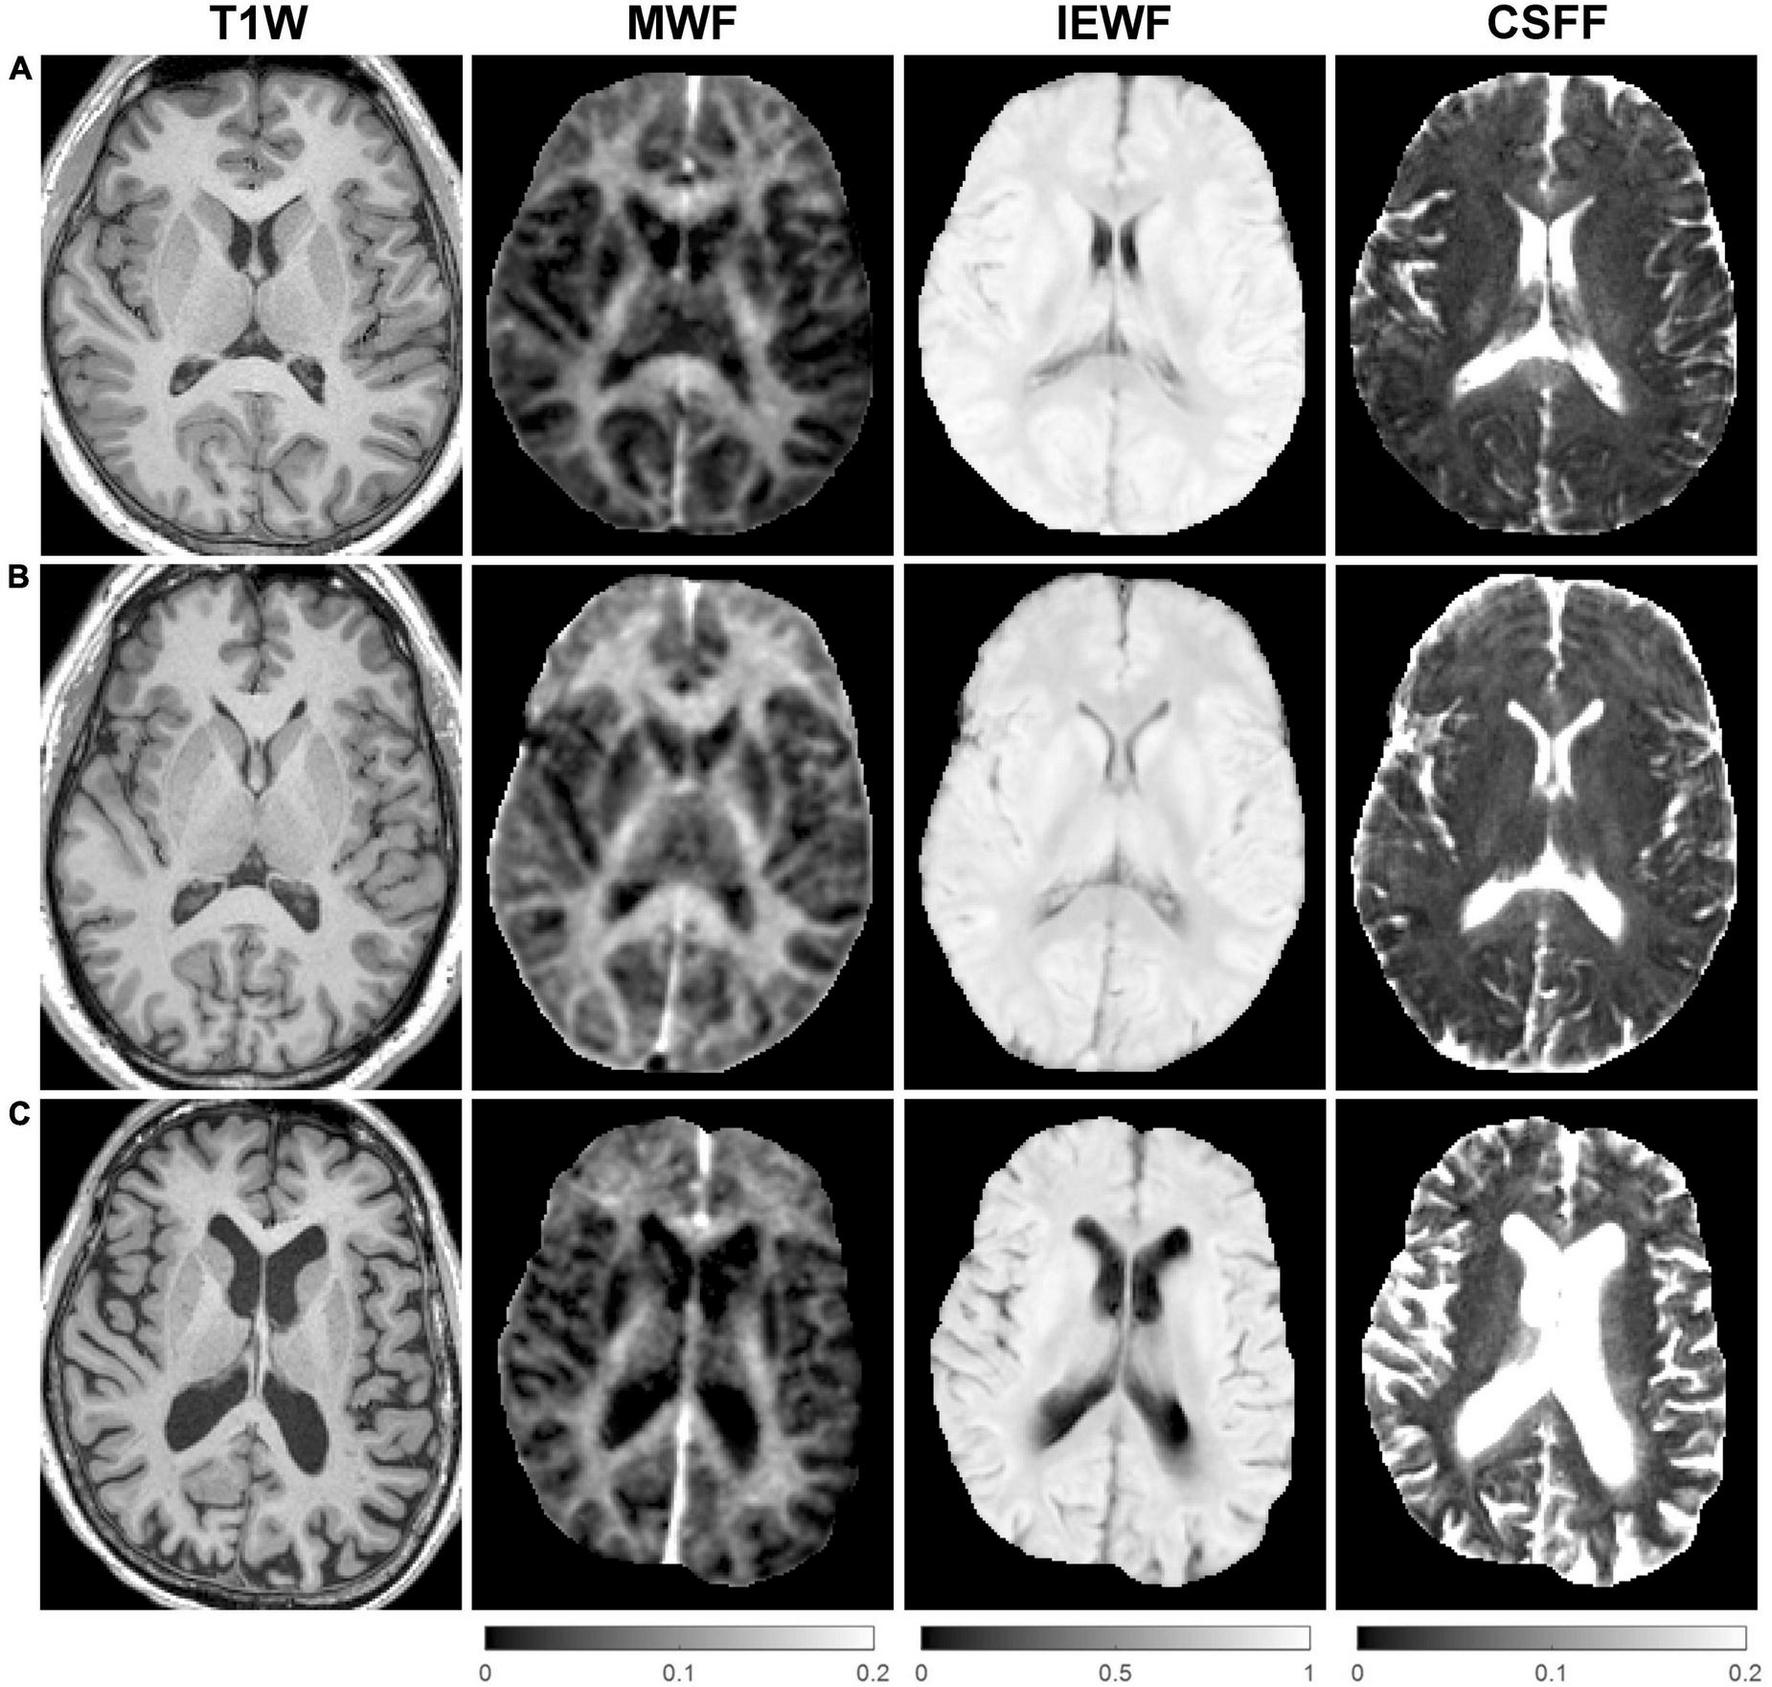

Figure 2 shows representative axial mid-brain WF maps obtained by the FAST-T2 sequence from 3 subjects. Compared to the younger 22-year-old (Figure 2A) and 46-year-old (Figure 2B) subjects, the 73-year-old subject (Figure 2C) showed prominent structural brain changes, including cerebral atrophy, cortical loss, and ventricular dilation seen on the T1W image, as well as increased values in the brain parenchyma on the CSFF map.

FIGURE 2

Representative axial mid-brain structural T1-weighted (T1W) magnetization-prepared rapid acquisition gradient echo (MPRAGE) images as well as corresponding myelin water fraction (MWF), intra/extra-cellular water fraction (IEWF), and cerebrospinal fluid fraction (CSFF) maps derived from fast acquisition with spiral trajectory and adiabatic T2prep (FAST-T2) data acquired from (A) a 22-year-old male, (B) a 46-year-old male, and (C) a 73-year-old female cognitively normal (CN) volunteers. Note the marked increase in cerebral atrophy, cortical loss, and lateral ventricular volume on the T1W image, and higher parenchymal CSFF values, in the latter subject compared to the younger subjects.